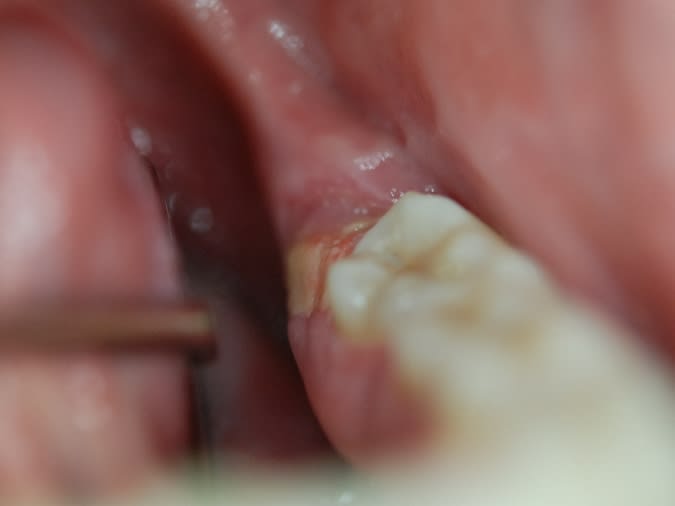

Jeune de 25 ans aucuns pb de santé, pas d'herpès, non fumeur. Aucuns d'antécédent médicaux. Pas de médicaments.

Grosses douleurs au niveau de la muqueuse derrière la 38. ( cf photo )

Aucuns pb dentaires, la 38 est bien sortie, la radio est parfaite.

je l'ai vu hier c'était rouge inflammatoire ( bien rouge ) , ce matin ça fait une genre de croûte jaune.

Le fond "beurre frais" me fait penser à un gros aphte.

on reste sur de la photo un peu floue, mais les 2 points blancs tout au fond , plus l'aspect que je ne trouve pas "aphteux" ainsi que la durée et la non amélioration me feraient adresser en dermato buccale ou autre, pour identifier cette ulcération.